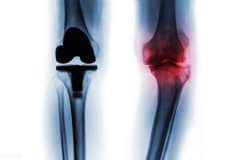

• 什么情况需要关节置换

当所有非药物和药物疗法都无效,骨关节炎已经发展到晚期,患者遭受持续严重的关节疼痛和功能障碍时,可考虑进行关节置换术。医生会根据患者的年龄、体重、活动水平、膝关节大小,形状以及整体健康状况制定手术方案,也不一定换掉整个关节,也可换掉一部分关节(单髁关节置换术),大部分患者手术次日就可下地先走,康复后可很大程度的恢复日常功能和生活质量。不过人工关节毕竟有使用寿命,因此骨关节炎的治疗原则是:从保守无创治

什么是膝关节表面置换? 膝关节表面置换就是对膝关节表面的软骨进行置换,当我们的膝关节表面磨损掉以后,我们就需要把2mm的软骨像镶牙手术一样进行替换,替换成钛合金的。 关节置换用的骨水泥长什么样? 骨水泥是聚甲基丙烯酸甲酯,由一包粉剂和液剂组成,把两者混合起来搅拌一下就会逐步成为固态,变成作用在人体上的骨水泥。膝关节假体通过背面和骨水泥结合,这样就会更加牢固。 膝关节置换如何